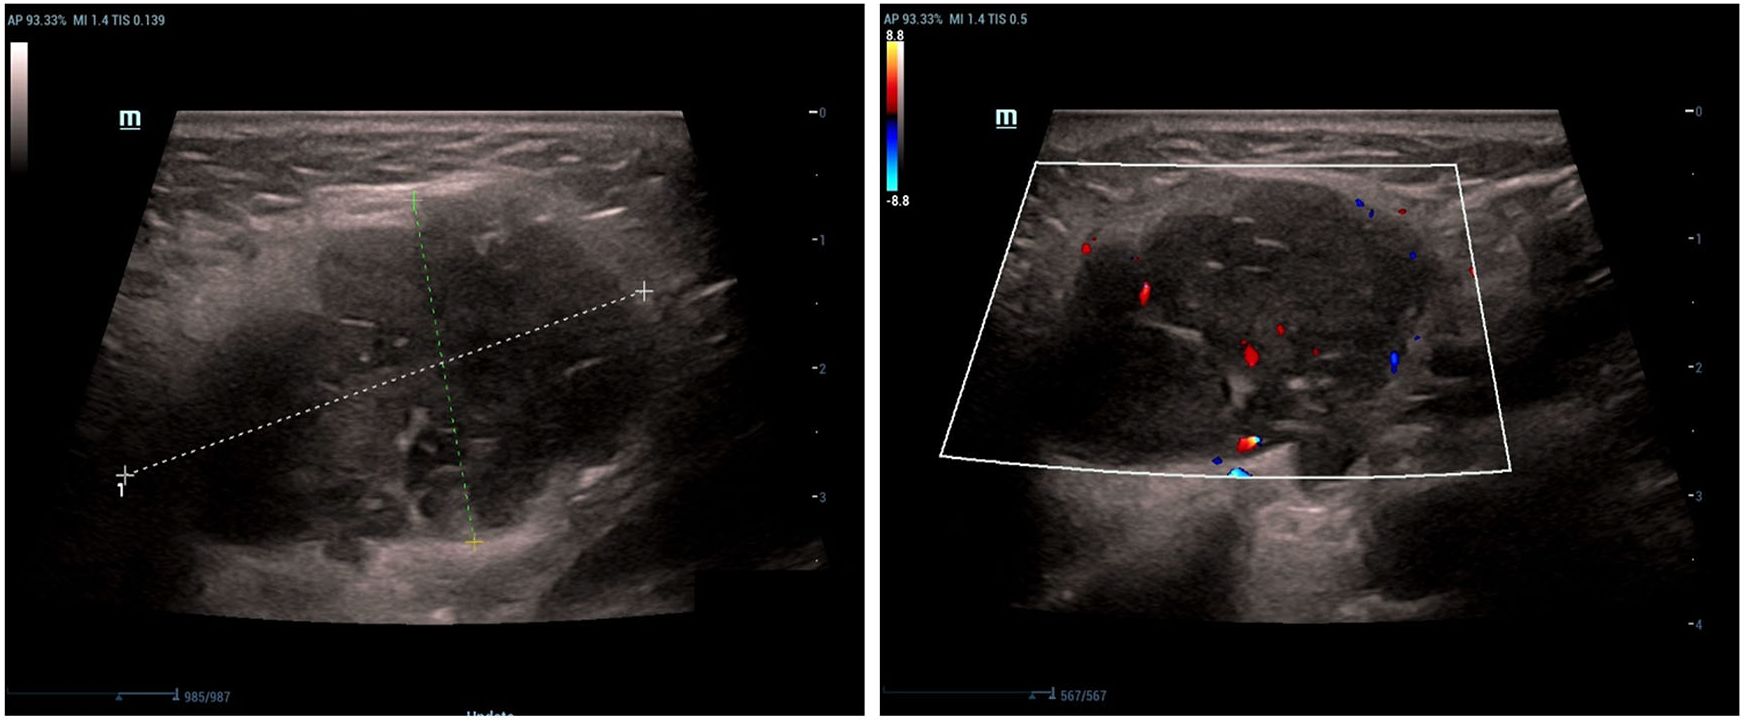

Background: Sebaceous lymphadenocarcinoma (SLAC) represents an extremely rare parotid malignancy, hypothesized to originate through malignant transformation of sebaceous lymphadenoma. To date, fewer than ten histopathologically confirmed cases have been documented globally. Case summary: A 33-year-old female presented with a persistent, painless left parotid mass that persisted despite anti-infective therapy. The patient underwent a comprehensive diagnostic workup prior to surgical resection. Histopathological examination of the specimen revealed sebaceous lymphadenoma with distinct foci of malignant transformation to SLAC, confirming a localized malignant process. Based on a review of the literature, this case represents the eighth reported instance of SLAC and the third with pathologically confirmed lymph node metastasis. Conclusion: SLAC most commonly presents as a painless parotid mass. Surgical resection is the cornerstone of therapy, with individualized use of radiotherapy. While early outcomes may be favorable, long-term surveillance is essential. International collaboration is urgently needed to establish registries and define standardized management guidelines for this exceedingly rare malignancy.